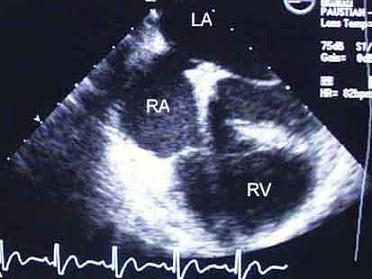

问题 女,3岁半,体检是发现胸骨下缘近心尖区可听到ⅡⅢ级收缩期杂音。经超声心动图检查,如图,确诊为房间隔缺损。杂音产生的机制是由于 ( )

选项 A、右心室流出道相对狭窄 B、二尖瓣相对狭窄 C、右心房血流量增加 D、三尖瓣相对关闭不全 E、血流通过房间隔缺损时

答案 D